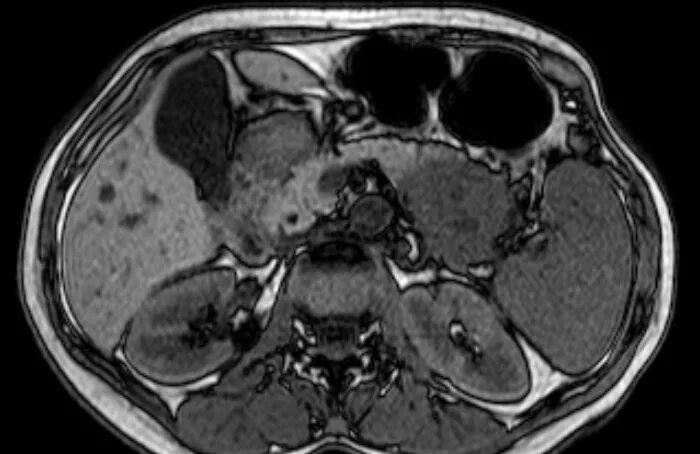

Мрт кисты поджелудочной